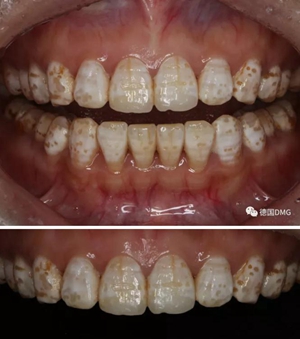

1,術前照片,全口氟斑牙,前牙表面釉質(zhì)白堊色+黃色斑點+凹坑缺損。

術前正面?zhèn)让嬲掌?/span>

治療前和治療后的對比,患者很高興很滿意。